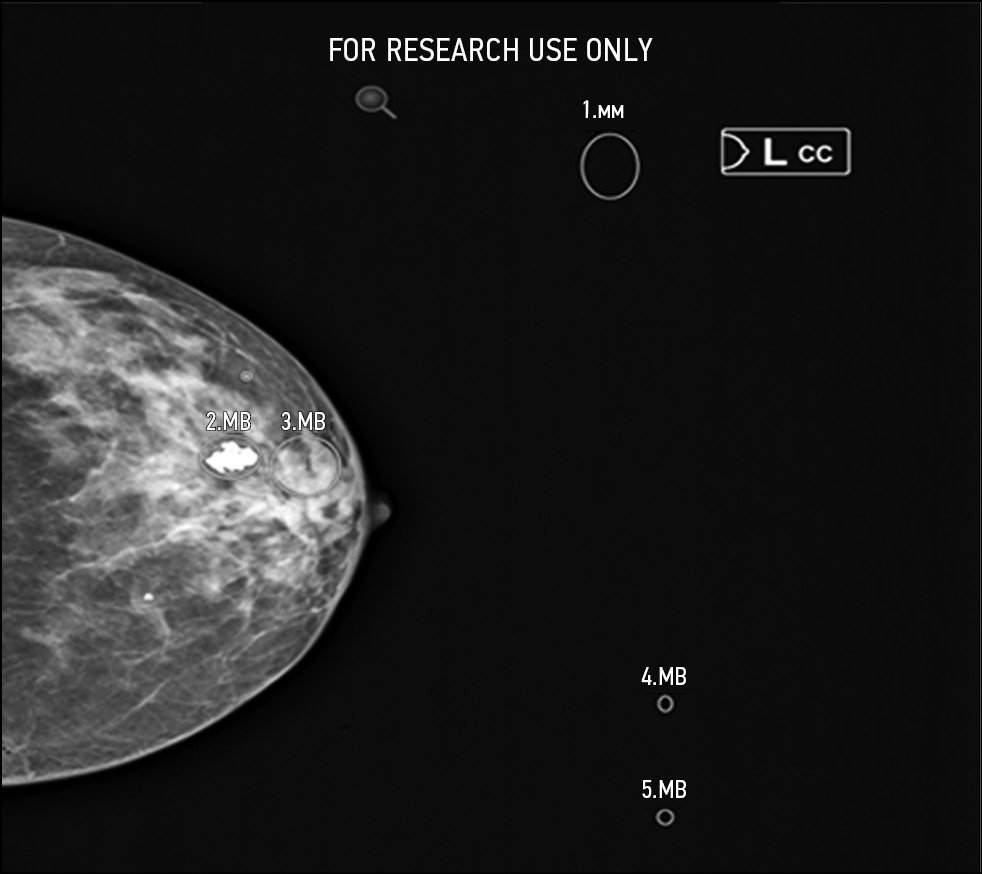

Fig. 4. Defect: off-target markings; Modality: mammography.

- Defects that affect the safety of patients and work of HCPs: failure to implement functions declared by the manufacturer; comments that influence a radiologist or complicate their work; and irreversible damage to original research data. This group includes, for example, Group D (D2, D3, D4) and F defects. Separately, a D7 defect (absence of a warning label “For research/scientific use only”) should be considered. This defect can only occur in the research setting and can never occur when using AI-based software as a medical device.

- Defects that do not affect the safety of patients but affect the work of HCPs: functional defects that do not conform to generally accepted standards for the presentation of research interpretation results. This group includes Group E and C (C1, C2, C3) defects.